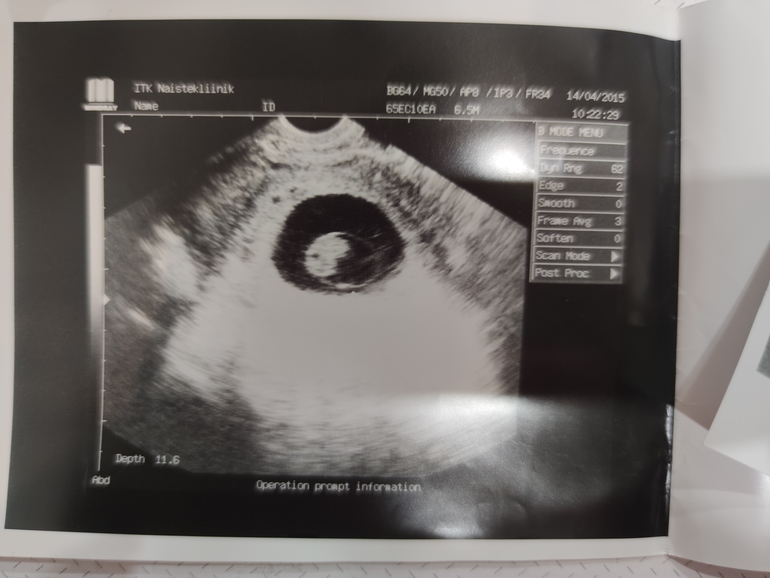

Счас дам 3 фото, узи во всех случаях вагинальное, срок по М 7-8 недель :)

Младший сын совпал?